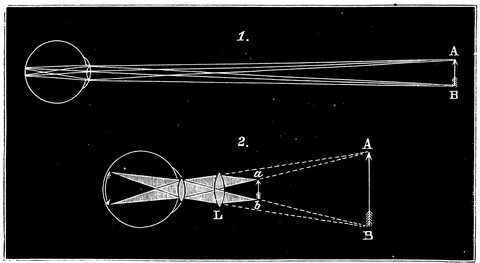

| 35. | Diagram showing path of rays when viewing an object at an easy distance | 70 |

| 36. | Action of short-sighted eye | 71 |